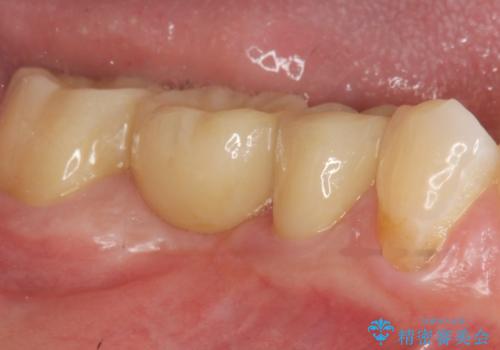

- 7万円 セラミックインレー費用は治療当時の料金となります

しっかりと虫歯を取り除き、精密なインレーを装着することで虫歯の再発を防ぎ長期的な予後を期待できる環境を整えます。